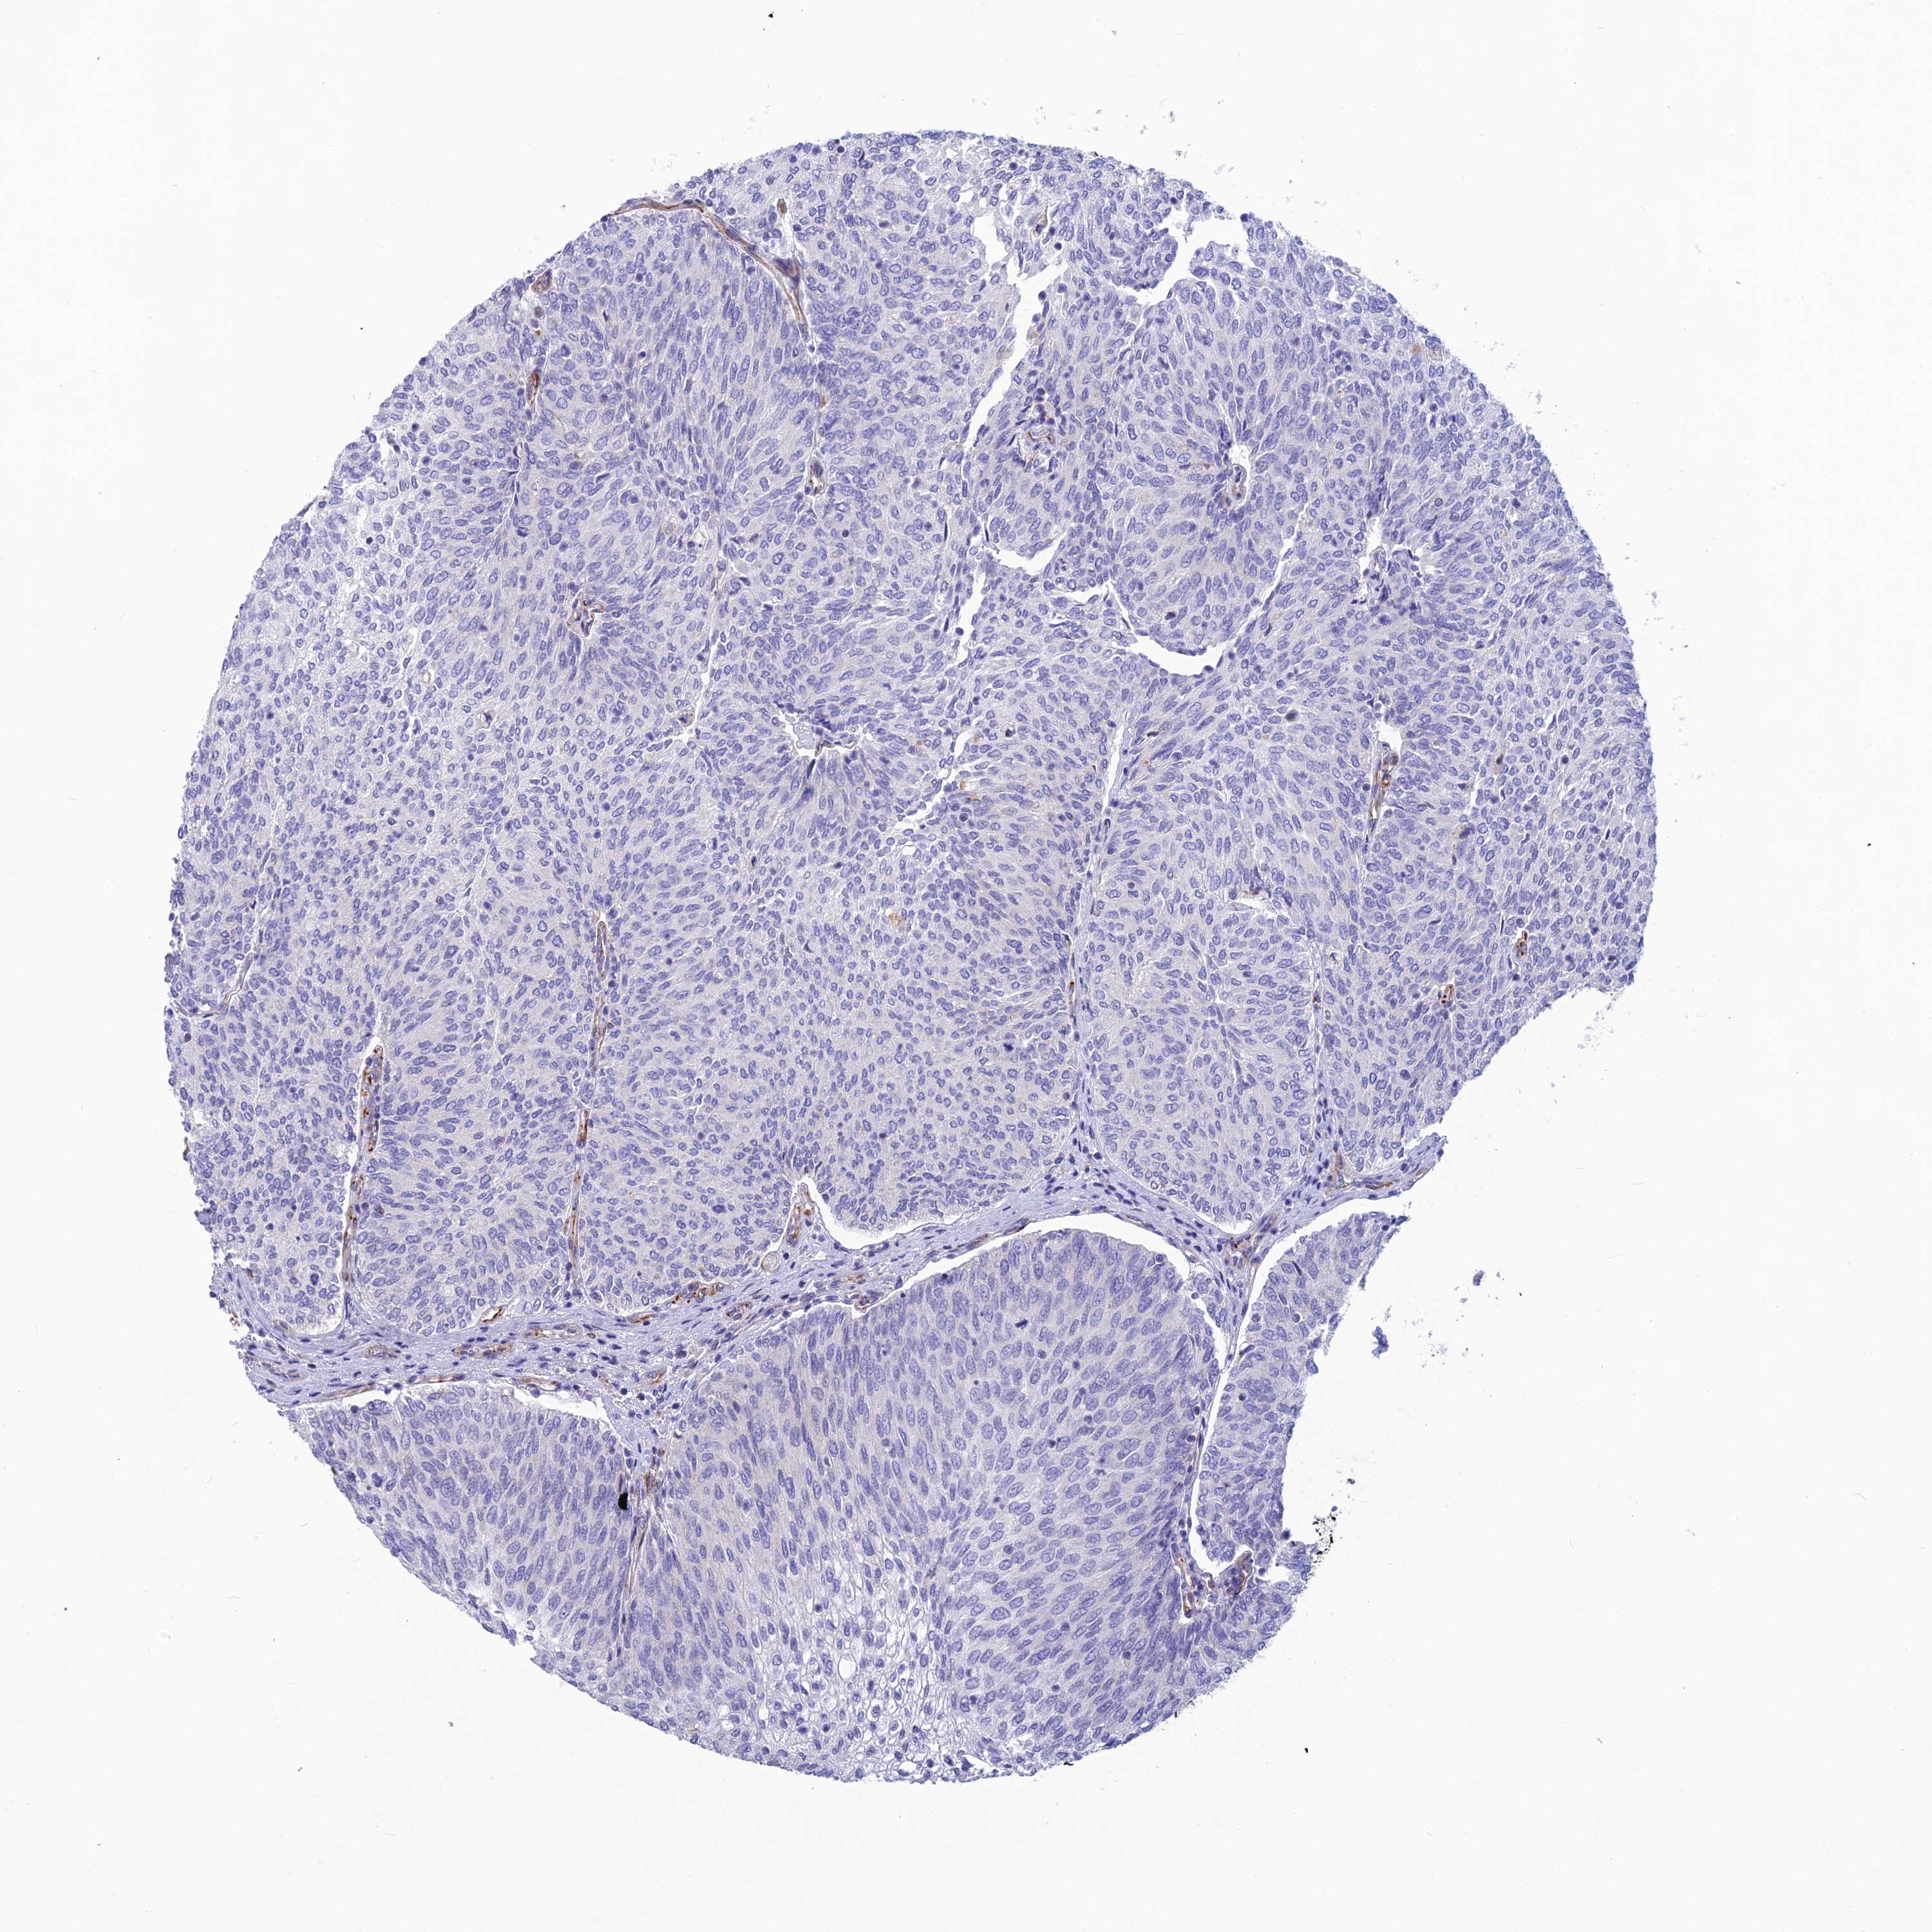

UROTHELIAL CANCER - Protein expressioni

A mouse-over function shows sample information and annotation data. Click on an image to view it in a full screen mode. Samples can be filtered based on level of antibody staining by selecting one or several of the following categories: high, medium, low and not detected. The assay and annotation is described here.

Note that samples used for immunohistochemistry by the Human Protein Atlas do not correspond to samples in the TCGA dataset.

Antibody stainingi

Antibody staining in the annotated cell types in the current human tissue is reported as not detected, low, medium, or high, based on conventional immunohistochemistry profiling in selected tissues. This score is based on the combination of the staining intensity and fraction of stained cells.

Each image is clickable and will lead to virtual microscopy that enables deeper exploration of all samples and also displays staining intensity scores, fraction scores and subcellular localization as well as patient and tissue information for each sample.

Antibody HPA044748

Antibody HPA050397

Urothelial carcinoma, High grade

Urothelial carcinoma, Low grade